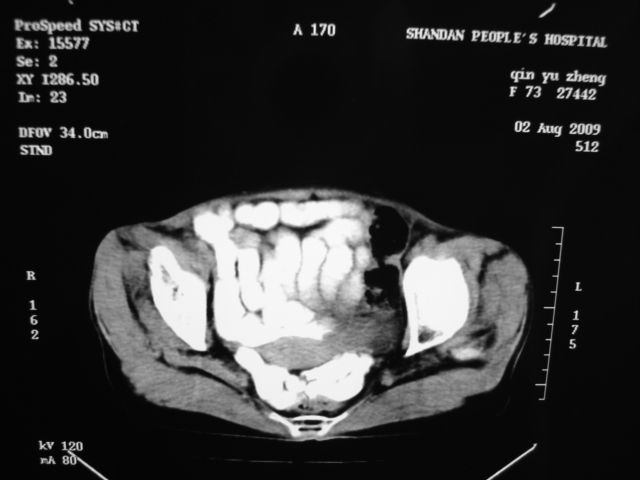

同事奶奶,73岁,腹痛一年,夜晚较重,潜血+++,拒绝增强,考虑左肾ca并腹膜后转移;请各位老师帮忙看看,谢谢!

左肾癌侵及输尿管上段,腹膜后多发淋巴结转移,脾脏钙化灶。至于潜血+++,要考虑消化道病变,本次ct片肠腔未见明显异常。

1)考虑左肾癌侵犯肾盂并腹膜后淋巴结转移。2)脾脏钙化灶。

考虑左肾癌侵犯肾盂并腹膜后淋巴结转移。